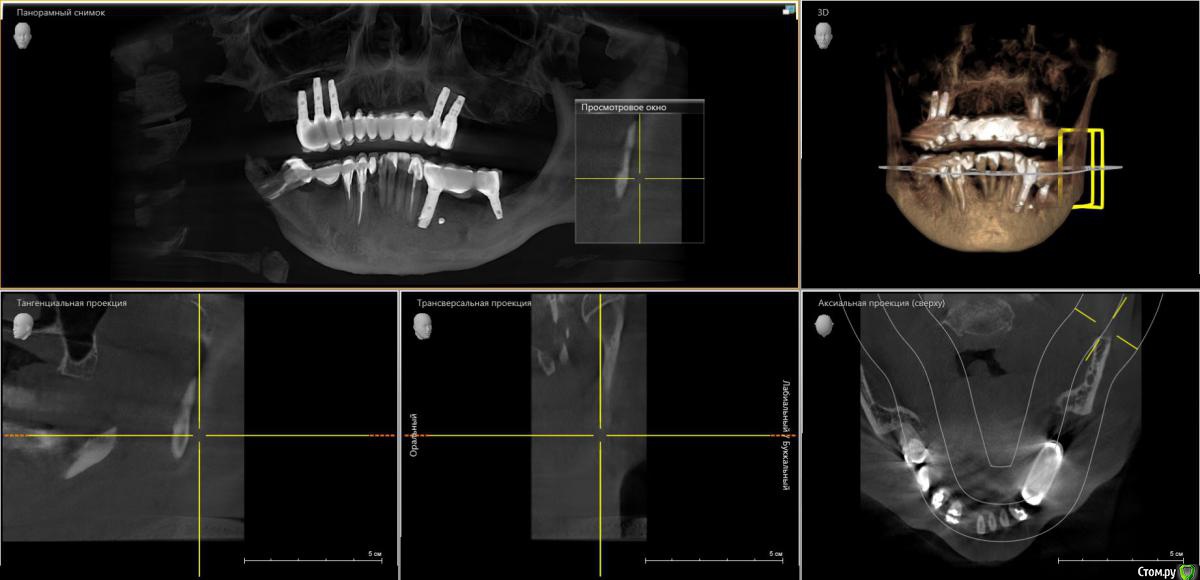

Чеширский Кот Опубликовано 24 декабря, 2019 Поделиться Опубликовано 24 декабря, 2019 (изменено) Здравствуйте дамы и господа. Появилась проблема с имплантами (стоят уже 4 года), или с десной (?), боль появилась на верхней челюсти, рядом с тремя имлантами. Боль легкая ноющая, с промежутками болит/не болит, никаких выделений с десны нет, не кровоточит. На прошлой неделе был у врача (не у того, который ставил), сделал КТ и осмотр, сказал все нормально, импланты не шатаются, держатся крепко, лишь небольшое воспаление десен во всей полости рта,и еще сказал, что немного опустилась десна, но это произошло через года 1,5-2 после установки. Не может это важно, но на десне появился маленький белый прыщик (?) + на внутренней стороне щеки прыщик но только красного цвета, как раз где возникают боли. В чем может быть причина болей? Помогите пожалуйста. Снимок прикреплен. https://cloud.mail.ru/public/3VN2/2VwCwjFhc Изменено 24 декабря, 2019 пользователем Чеширский Кот Ссылка на комментарий

Irouil Опубликовано 24 декабря, 2019 Поделиться Опубликовано 24 декабря, 2019 Срез малоинформативный, но, на первый взгляд, явных проблем с имплантами нет. Смущает вид конструкции, теоретически это может привести со временем к перегрузке, но это уже в ветку ортопедии вопрос. Прыщик сфотографировать бы, ну и можно попробовать у каждого имплантата срезы отскриншотить, но без очного осмотра с Вашим анамнезом и тем, что показывают снимки, скорее всего причину болей не выявить Ссылка на комментарий

Irouil Опубликовано 25 декабря, 2019 Поделиться Опубликовано 25 декабря, 2019 Вокруг имплантатов нет плотной слизистой, со временем это может привести к нежелательным дегенеративных процессах в тканях. Я бы рекомендовал консультацию пародонтолога, возможно потребуется снять конструкцию (она должна откручиваться), провести пересадку плотной десны с неба. Криминала не видно, но действовать надо Ссылка на комментарий